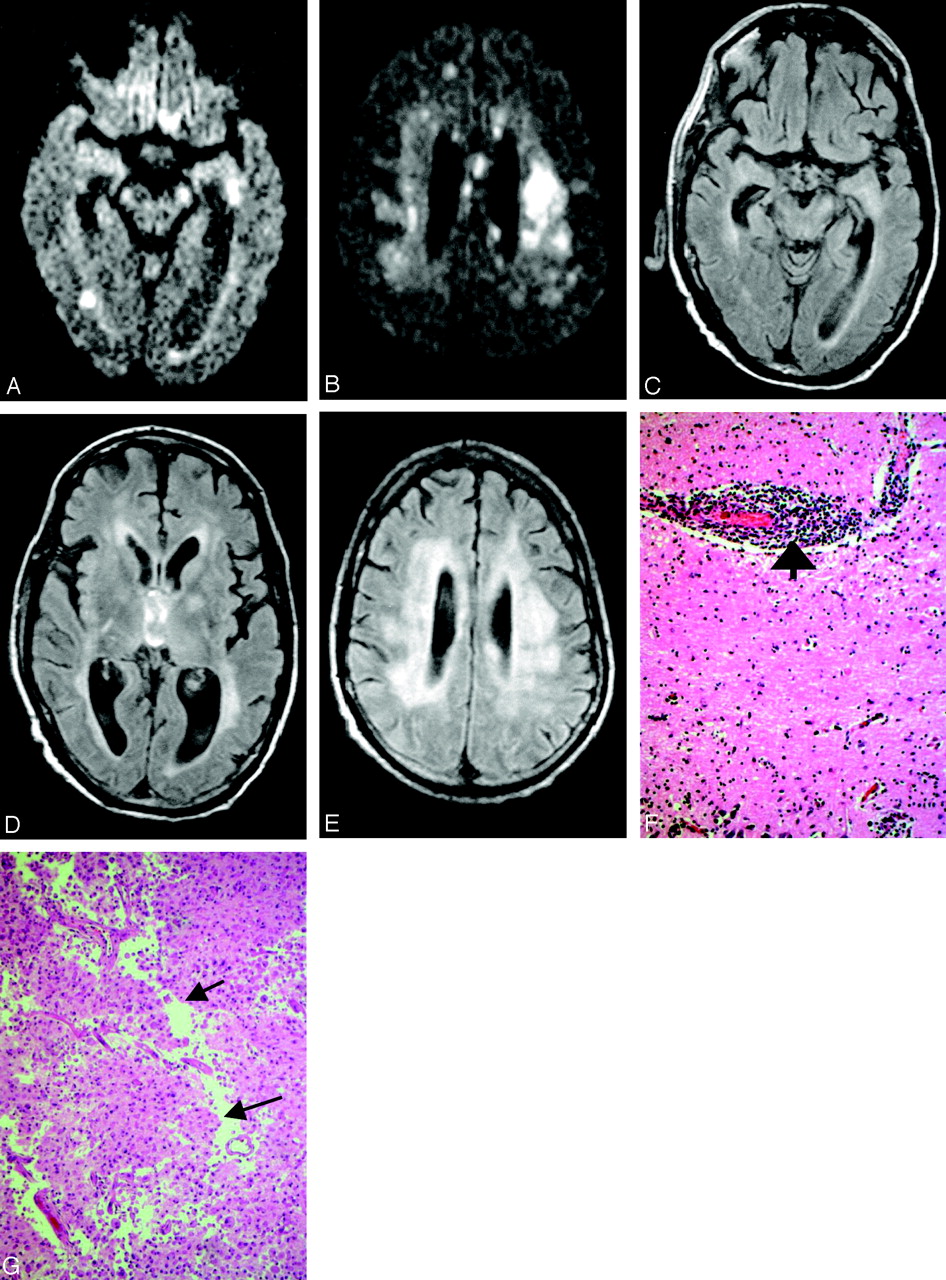

Patient 17, a 49-year-old woman with history of non-Hodgkin lymphoma in remission presented with fever. Work-up was negative for recurrence. The first MR imaging of the brain shows abnormality in the left mesial temporal lobe on trace DW image (A) and ADC (B), though the finding is subtle on the FLAIR sequences (C). At the time of imaging, the findings raised the question of herpes encephalitis, for which the patient was originally treated. Following deterioration of the mental status and development of upper extremity weakness, a second MR imaging was obtained. The abnormality is now apparent on the FLAIR sequences and has progressed to involve not only the contralateral mesial temporal structures, but also the substantia nigra (D), as well as the mesial and dorsal aspect of the thalami (E). Further clinical deterioration with established “polio-like” symptoms prompted a new MR imaging 11 days later, which demonstrated new areas of involvement with resolution of improvement of prior lesions. Images of this MR imaging show increased signal intensity in the dentate nuclei on FLAIR (F) and DW (G) images and right thalamus on FLAIR image (2 hours) and DW image (I) and improvement of the mesial temporal lobe and midbrain abnormalities (J). Focus of T2 hyperintensity is seen in the right red nucleus on FSE T2-weighted image (K). On J, note site of biopsy in the lateral aspect of the left temporal lobe that was negative for herpes encephalitis. The fourth MR imaging was obtained upon patient’s discharge to a nursing facility. DW images show increased signal intensity in the cerebellar hemispheres and right branchium pontis (L), vermis (M), and the right red nucleus (N). Cerebellar hemisphere abnormalities were more conspicuous on DW than FLAIR or FSE T2-weighted images. FSE T2-weighted (O) and DW (P) images through the level of the basal ganglia demonstrate persistent abnormality in the right thalamus and new lesions in the right globus pallidus and left thalamus, whereas the FLAIR image demonstrates involvement of the right corona radiata (Q) as well.

The WNV as a member of flaviviridae family not only has close antigenic relationship with Japanese and St. Louis encephalitides; it also shares some of the imaging findings. Reports on St. Louis encephalitis are relatively limited, but MR imaging findings in Japanese encephalitis have been described extensively (11–14). Signal intensity abnormalities on FLAIR, FSE T2-weighted and, in many cases, DW imaging sequences observed in the thalami, basal ganglia, and midbrain were common findings in our patients. A common finding in 5 (32%) of our patients was the involvement of the mesial temporal structures (Table 1). Although it has been reported with Japanese encephalitis (11), increased intensity signal intensity on T2-weighted sequences in the mesial temporal structures in a clinical setting of encephalitis strongly suggests herpes simplex encephalitis and prompts immediate treatment. The pathologic background of WNV encephalitis, however, is quite different from that of herpes encephalitis, in light of the necrotizing nature of the latter. One of the patients (17) with serial MR images presented with mesial temporal lobe abnormalities (Fig 2A–D), which progressed and then resolved only to involve other areas of the brain. The lack of necrotizing process in WNV encephalitis actually explains the absence of any residual signal intensity abnormality on the follow-up studies. (Fig 2J).

Midbrain involvement was noted in only 3 patients (Table 1); signal intensity abnormalities present in the cerebral peduncle and substantia nigra (Fig 2D, -J, and -K), as well as red nucleus (Fig 2N), are in accordance with prior case reports on Japanese and St. Louis encephalitides (13, 15). Involvements of the pontine tegmentum (Fig 1A and -B) and superior cerebellar peduncles (Fig 1C) were the first abnormalities to be noticed in one of the patients (2), who became ventilator dependent and progressed to develop flaccid paralysis. There were 4 patients who presented at some point with extremity weakness. All, with one exception (17), had MR imaging studies of the spine; abnormalities were seen in the gray matter and particularly the ventral horns in 2 of them, whereas enhancement of the conus medullaris and the cauda equina was seen in all 3. Prior reports have associated the flaccid paralysis with enhancement around the conus and along the cauda equina (2, 3). Anterior myelitis apparently contributes to the clinical picture as well (Figs 1E–G and 4A and -B). Abnormalities in the dentate nuclei, cerebellar white matter, and cortex were present in only one patient (Fig 2F, -G, -L, and -M) and are depicted on one of the follow-up MR imaging studies coinciding with newly developed “polio-like” symptoms. Unfortunately the patient’s spine was never imaged, so whether there were any additional findings of anterior myelitis and/or radiculitis remains unknown.